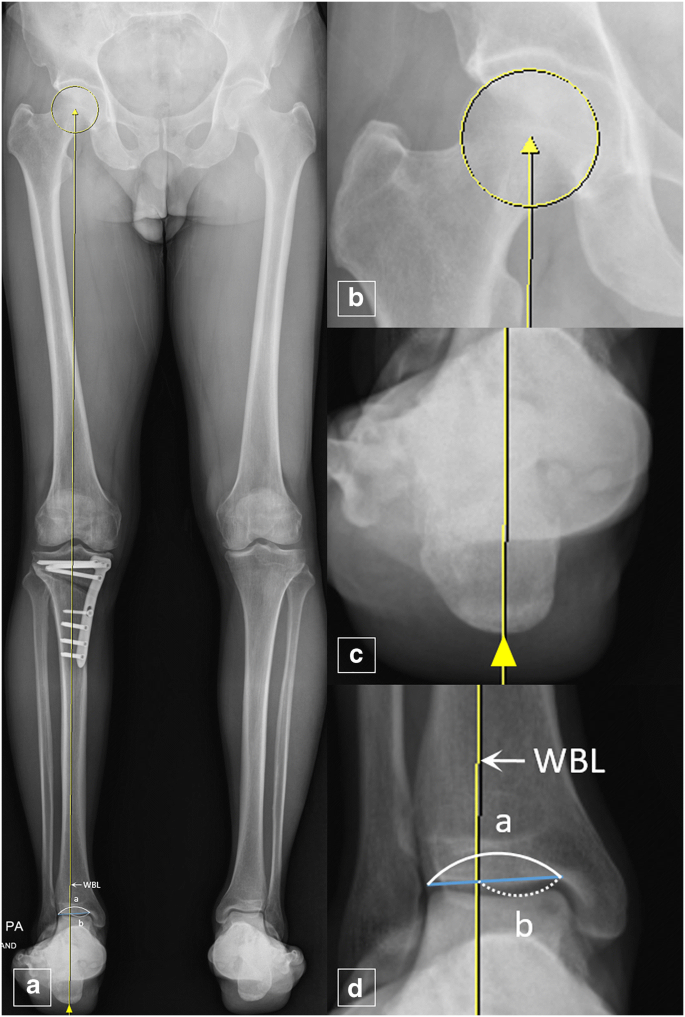

To understand knee deformity, you need to understand one anatomical concept: the weight-bearing line.

When you stand or walk, your body weight travels down a straight line from your hip to the ground. In a healthy knee, this line passes through the centre of the knee joint — distributing pressure evenly across the cartilage.

But here's the catch: that weight-bearing line naturally passes slightly toward the inner (medial) side of the knee. This means the inner compartment of your knee joint bears slightly more load than the outer compartment, day after day, year after year.